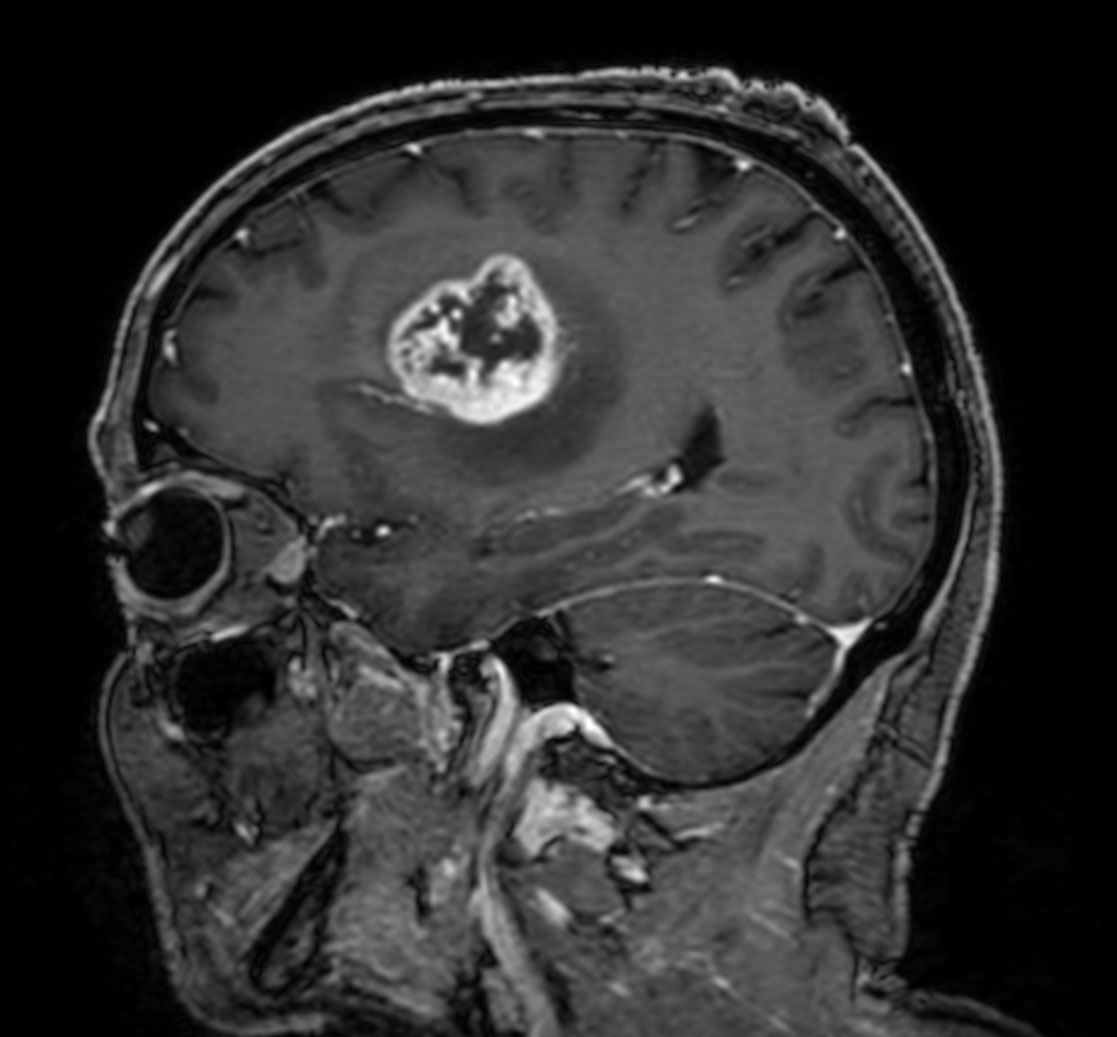

Sagittal T1w 3D TFE

-